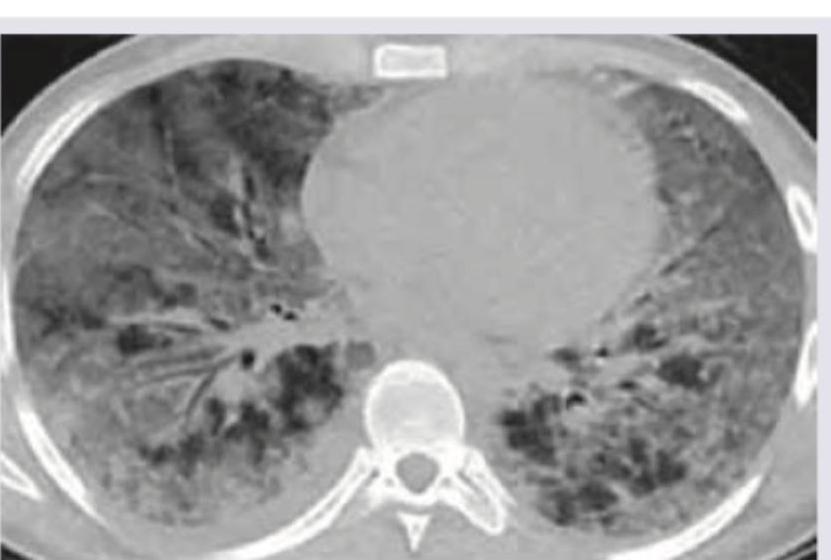

The CT chest shows presence of:

Explanation: ***Pulmonary alveolar proteinosis*** - CT images of pulmonary alveolar proteinosis often show diffuse, bilateral ground-glass opacities with superimposed **interlobular and intralobular septal thickening**, creating a characteristic **crazy-paving pattern**. - This pattern, as seen in the image, is caused by the accumulation of lipoproteinaceous material within the alveoli and is a hallmark of the disease. *Interstitial lung disease* - While some forms of interstitial lung disease can cause ground-glass opacities and septal thickening, the **"crazy-paving" pattern** seen so clearly and diffusely here is not typically their most characteristic finding. - ILD often presents with **reticular opacities**, honeycombing, or traction bronchiectasis, which are less prominent or absent in this specific image. *Bronchiectasis* - Bronchiectasis is characterized by **irreversible dilation of the bronchi**, usually accompanied by wall thickening. - This condition would appear on CT as **dilated, thickened airways** (often described as "tram-track" opacities or "signet-ring" signs) and mucus plugging, which are not the predominant findings in the provided image. *Aspergillosis* - Pulmonary aspergillosis encompasses several forms, such as aspergilloma (fungus ball in a cavity), invasive aspergillosis (nodules, halo sign, or cavitation), or allergic bronchopulmonary aspergillosis (mucoid impaction, bronchiectasis). - The diffuse ground-glass opacities with septal thickening seen in the image do not typically represent the primary radiological features of aspergillosis.

Explanation: ***Ground glass pattern*** - The CT scan shows diffuse hazy opacities that do not obscure the underlying bronchial and vascular markings, which is characteristic of a **ground-glass pattern**. - This pattern indicates a partial filling of airspaces, interstitial thickening, or a combination of both, often seen in conditions like **pneumonitis** or early acute respiratory distress syndrome. *Honeycomb pattern* - The image does not display the characteristic **thick-walled cystic airspaces** seen in a honeycomb pattern, which typically represents end-stage pulmonary fibrosis. - While there is some architectural distortion, it lacks the discrete, clustered cysts with clearly defined walls that define true honeycombing. *Crazy pavement pattern* - The crazy paving pattern is characterized by **ground-glass opacities superimposed with interlobular septal thickening**, which is not clearly and extensively demonstrated in this scan. - While some ground-glass is present, prominent septal thickening creating a polygonal pattern is not the predominant feature. *Normal scan* - The scan clearly shows widespread **abnormal opacities** throughout both lungs, indicating significant underlying pathology. - A normal chest CT would show uniform lung parenchyma with clear bronchial and vascular markings without any significant areas of increased attenuation.